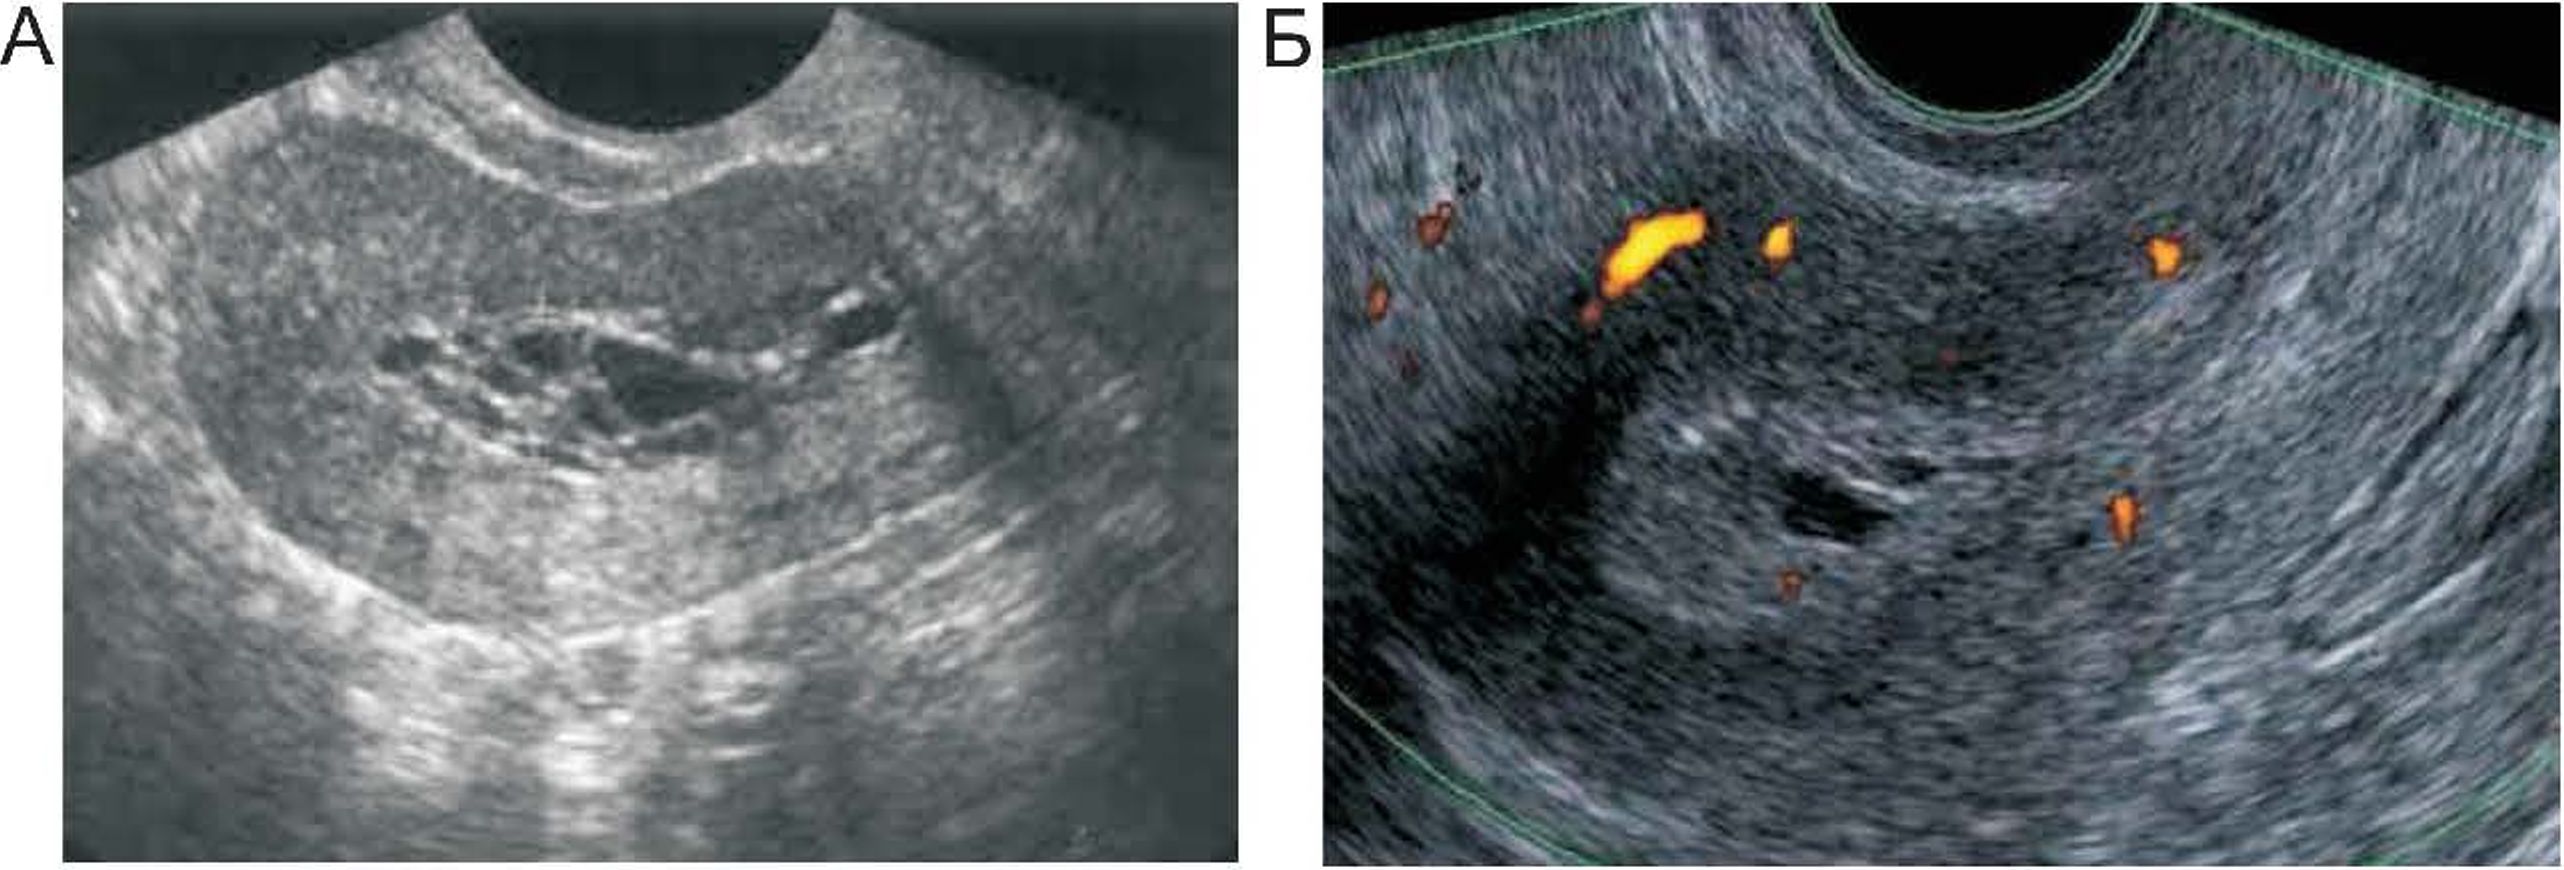

Морфологические особенности метаплазии эндометрия, развивающейся на фоне приема тамоксифена, показали, что в строме развиваются характерные признаки гипертрофии с явными признаками усиленной пролиферации базального слоя. В то же время, поверхность самого эндометрия минимальна, достаточно гладкая и плотная, что затрудняет забор материала для гистологии путем пайпель-биопсии. Интересно, что в большинстве случаев тамоксифеновые изменения в эндометрии имеют стромальую локализацию (рис. 4), а при развитии уже эндометриоидного рака преобладает паренхиматозная реакция (рис. 5).

РИС. 4. А. - стромальные изменения эндометрия после приема тамоксифена. Б. — кистозная метаплазия эндометрия

Также в тканях, видоизмененных тамоксифеном, определяется выраженная гиперэкспрессия рецептора GPR30/ G-белок рецептора эстрогена, особенно в образцах эндометриальной интраэпителиальной неоплазии, что вероятно и является причиной высокой пролиферативной активности базального слоя, в среднем, К1 67 в образцах находился в диапазоне от 30 до 40%. Также для эндометриальной интраэпителиальной неоплазии был характерен очаговый характер роста, без проникновения в строму, и наличие атипичных клеток, преимущественно железистого типа, потеря гена-супрессора РТЕК

Рис. 5. Экспрессия рецепторов GPER, в нормальном секреторном эндометрии и на тамоксифене.

Таблица 2. Экспрессия рецептора GPER и ER в зависимости от морфологических изменений, вызванных приемом тамоксифена, иммуногистохимическое исследование 34 образцов (рис. 5)